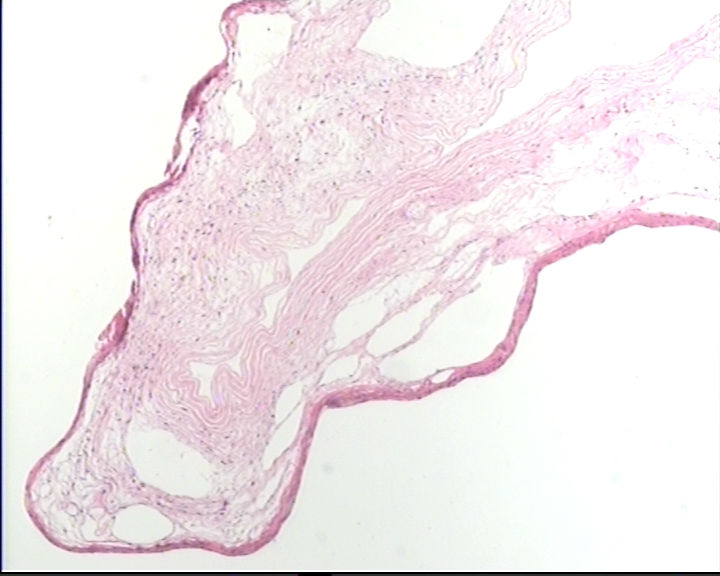

这一类型的卵巢囊肿该怎么发?

剖宫产时卵巢上面剥离下来的,7×6.5×2cm,囊壁菲薄,内容淡黄色清亮液体,内壁光滑

卵巢囊肿图3

名称:图3

仔细找找,如果确实没有明确的被覆上皮就报单纯性囊肿。

单纯囊肿。未见明确上皮成分,良性。

同意单纯性囊肿,没有被覆上皮。

未见被覆上皮,单纯性囊肿。